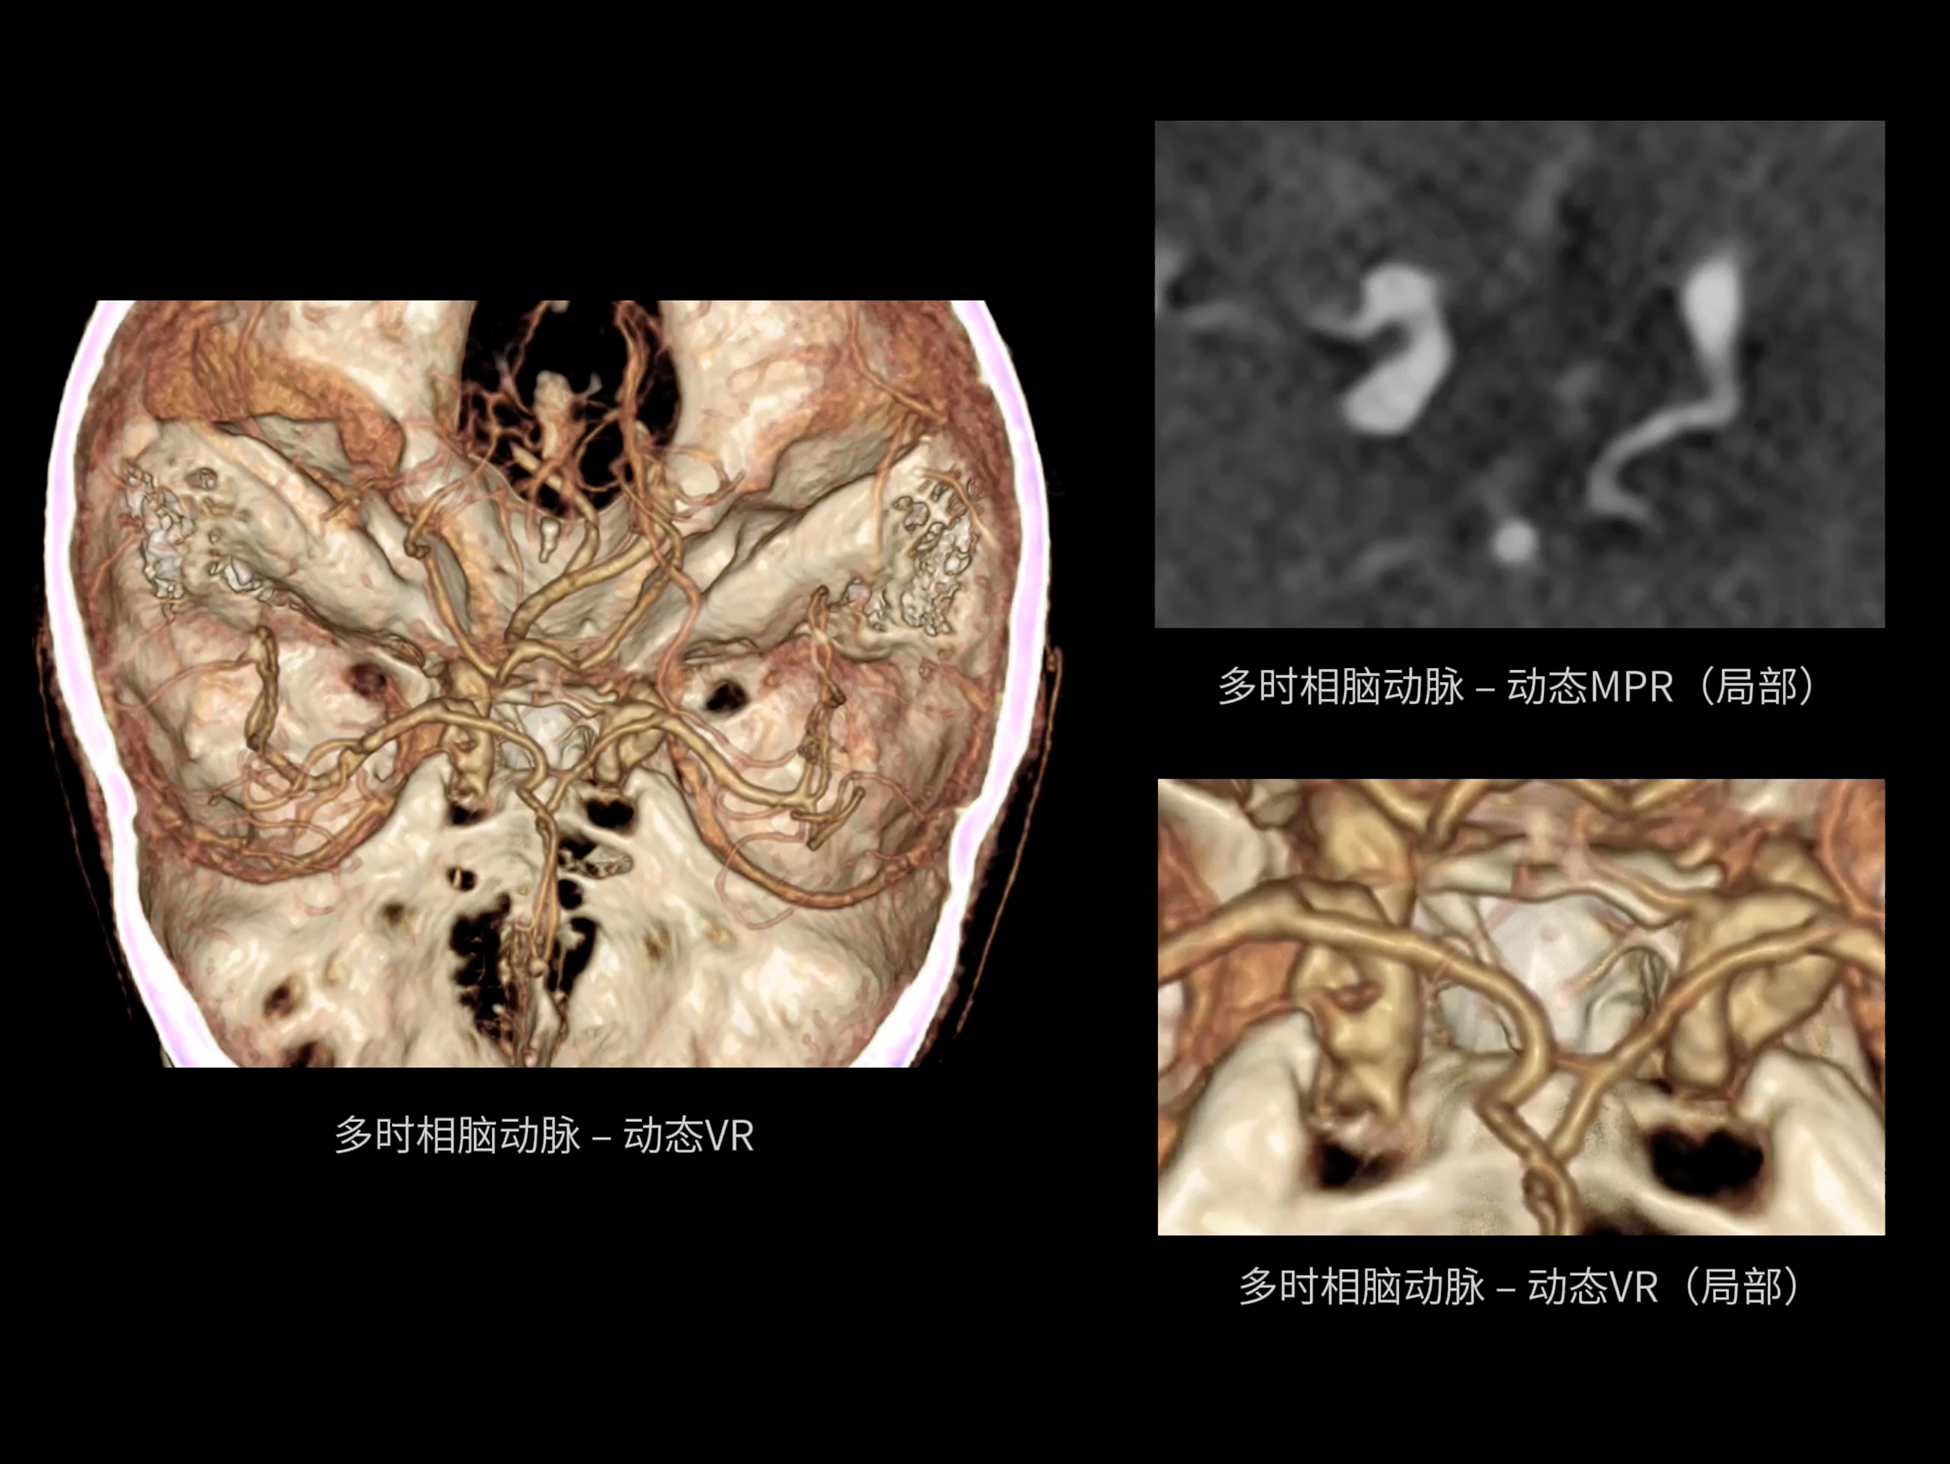

uCT SiriuX® 依托16cm超宽探测器与双源能谱技术,实现真正意义上的全身高清能谱成像。单次扫描同步获取灌注、能谱等多维定量参数,精准解析组织特性与病灶成分,为临床决策提供更深层次的诊断依据。

能谱成像可揭示丰富的物质与能量信息,其临床价值的充分释放有赖于完善高效的后处理分析平台。uCT SiriuX® 提供全面能谱高级分析工具,覆盖心血管、肿瘤、神经、骨科等多类临床场景。平台支持动脉增强分数分析(AEF)、细胞外容积分析(ECV)、肿瘤同源性分析、肺栓塞分析、骨髓水肿分析等多项评估,并提供多达10种基物质对成像,为精准诊断与科研探索提供坚实支撑。